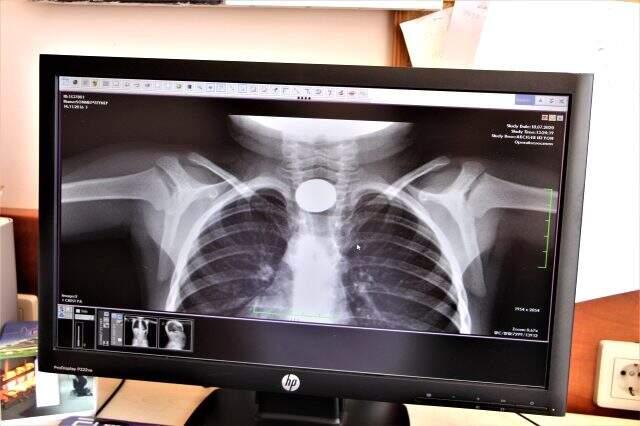

Çocuk Gastroenteroloji Hepatoloji ve Beslenme Bilim Dalı Başkanı Prof. Dr. Yaşar Doğan, müdahale ederek cisimleri nefes ve yemek borusu ile mideden gerçekleştirdiği operasyonlarla çıkardı. Haftada 3 ile 5 arasında vakaya müdahale ettiklerini belirten Prof. Dr. Doğan, yabancı cisim yutması şikayeti ile kendilerine gelen çocuklarda başta madeni para olmak üzere pil, misket, toplu ve çengelli iğne, vida, saat pili, düğme, tel toka, gazoz kapakları, küçük oyuncaklar ve çok sayıda küçük metal çıkarttıklarını söyledi.

Her türlü yabancı cisim yutması şikayeti ile karşılaştıklarını belirten FÜ Çocuk Gastroenteroloji Hepatoloji ve Beslenme Bilim Dalı Başkanı Prof. Dr. Yaşar Doğan, "Özellikle son dönemlerde madeni paraların kullanıma girmesiyle birlikte madeni para başta olmak üzere çocukluk döneminde özellikle ilk 6 ay ve 18 yaş arasındaki hemen hemen her yaş döneminde çok fazla sayıda aylık olarak bize yabancı cisim yutulması söz konusu. Bu yabancı cisim örneklerde de görüldüğü gibi çoğunlukla madeni para olmak üzere toplu iğne veya günlük hayatta kullanılabileceğimiz madeni eşyalar, gazoz kapakları veya çakmak başlıkları, çengelli iğneler olmak üzere hemen hemen her türlü paralar çocuklar tarafından yutulmaktadır" dedi.

Erken dönemde risk faktörlerin olduğuna dikkat çeken Prof. Dr. Doğan, "Bunlar bazen yemek borusuna kaçmakta bazen de nefes borusuna kaçmaktadırlar. Tabi bunun ayrımını dikkatli bir şekilde yapmak lazım. Özellikle nefes borusuna kaçanlar çok ciddi hayati risk teşkil etmektedirler. Özellikle yemek borusuna kaçanların da çocuklarda çok ciddi yutma problemleri, salya akması, ciddi boğaz ağrısı ve yutma güçlüğü oluşturduğundan dolayı erken dönemde bize getirilmesi, gerekli olan endoskopik işlemleri ile başarılı bir şekilde çıkarılmaktadır. Burada görüldüğü gibi çok sayıda yabancı cisimlerin son bir buçuk ile iki yıl arasında çıkarıldığını görmekteyiz. Bunların kat kat fazlası da envanterimizde bulunmakta" şeklinde konuştu.